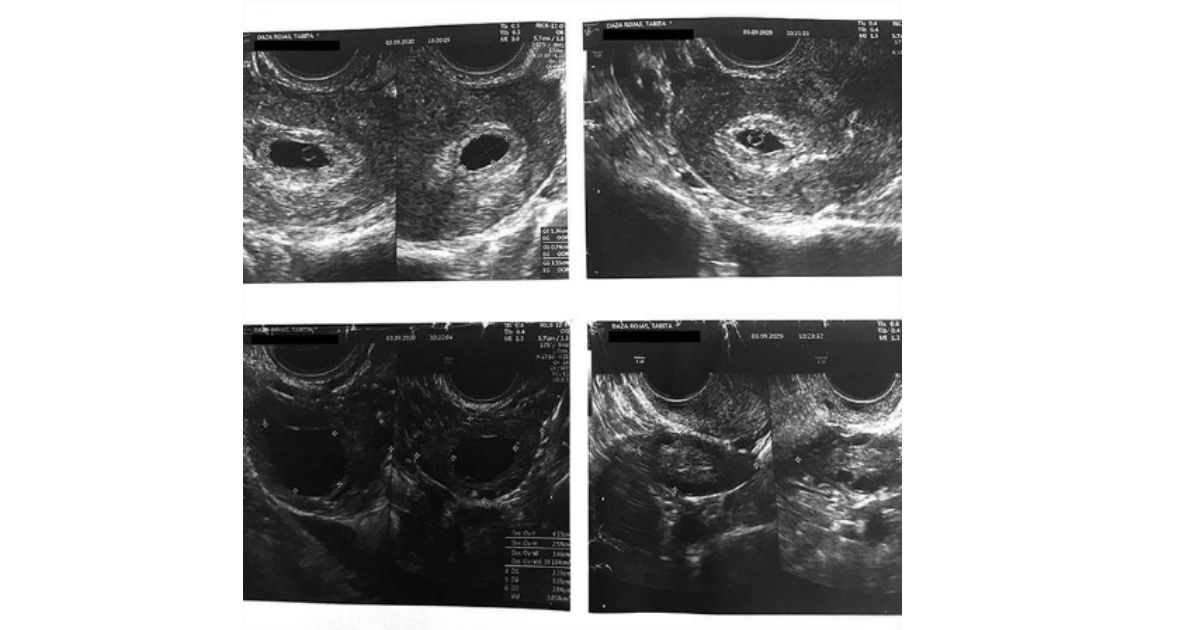

In March 2020, Tabita Daza Rojas, 29, discovered that she had an ovarian cyst, and her physician at that time worried that it was caused by her contraceptive implant.

The doctor at the local health clinic advised Rojas to take the pill instead and prescribed Anulette CD. She did not think much about the contraceptive switch as she had taken pills before and agreed that it made perfect sense for her health.

However, just five months after Rojas began taking Anulette, she found out she was pregnant again.

“I was about to finish the second [box of three prescribed] when I found out about the problem,” Rojas said, by the time she knew about the defect, she was already six weeks pregnant.